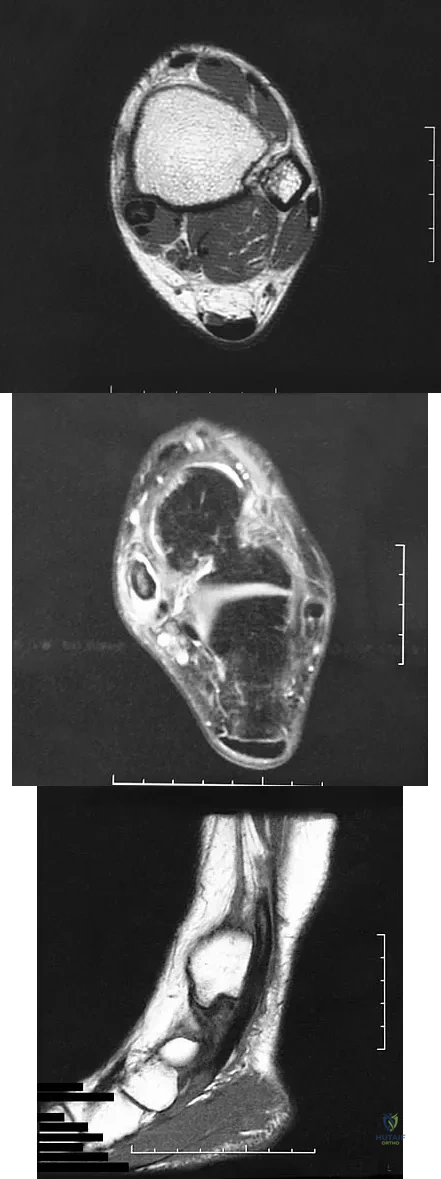

Question 55

A 37-year-old man with a history of congenital flatfoot reports worsening pain on the medial aspect of his ankle for the past year. The pain is worse with weight bearing and is better with rest and the use of an ankle brace. What findings are shown on the MRI scans shown in Figures 18a through 18c?

Explanation